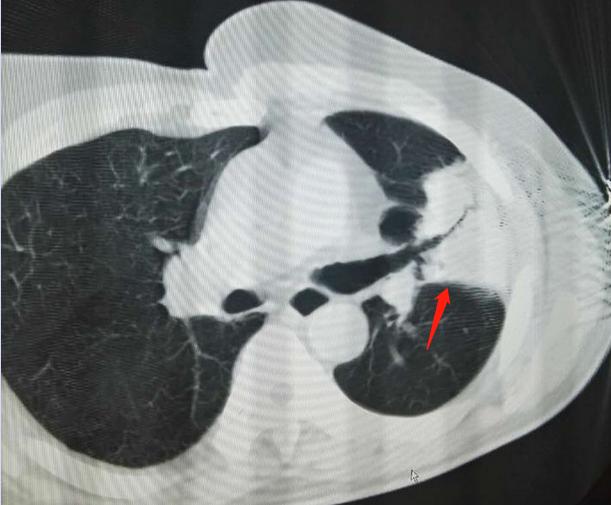

病例:男性,64岁,咳嗽、咳痰、乏力2个月,既往有肺结核病史。但是对比患者既往检查的片子,发现在钙化团块处新发软组织密度影,部分钙化灶被侵蚀掉了。